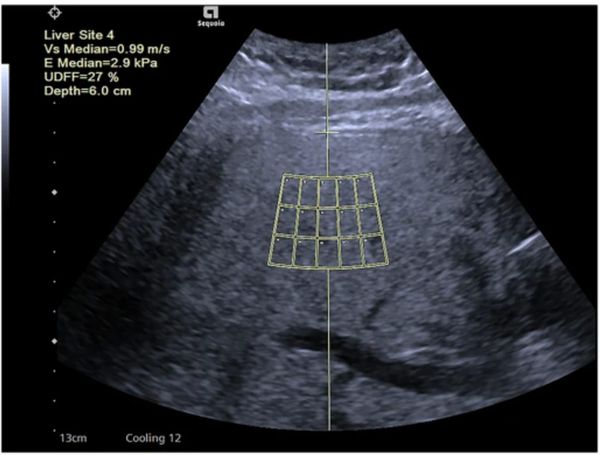

In a prospective comparison with prior criteria for evaluating hepatocellular carcinoma surveillance, the American Association for the Study of Liver Diseases (AASLD) version 2023 system offered significantly higher sensitivity.